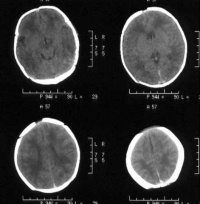

(2)头颅计算机扫描摄影(CT)检查:作头颅水平位横断面多层次摄片。对硬膜下少量出血蛛网膜下出血的显示较B超检查清楚,因此CT和B超互补检查可更提高诊断率。

1.有明确围产期缺氧史,特别是围产期重度窒息史患儿。 2.生后1周尤其头3天内出现异常神经症状,病情较重时前囟饱满、惊厥、中枢性呼吸衰竭等。 3.常合并吸入性肺炎,严重时可同时存在颅内出血。 4.颅脑CT及颅脑B超检查对诊断、分度、估计预后及鉴别诊断有一定意义。